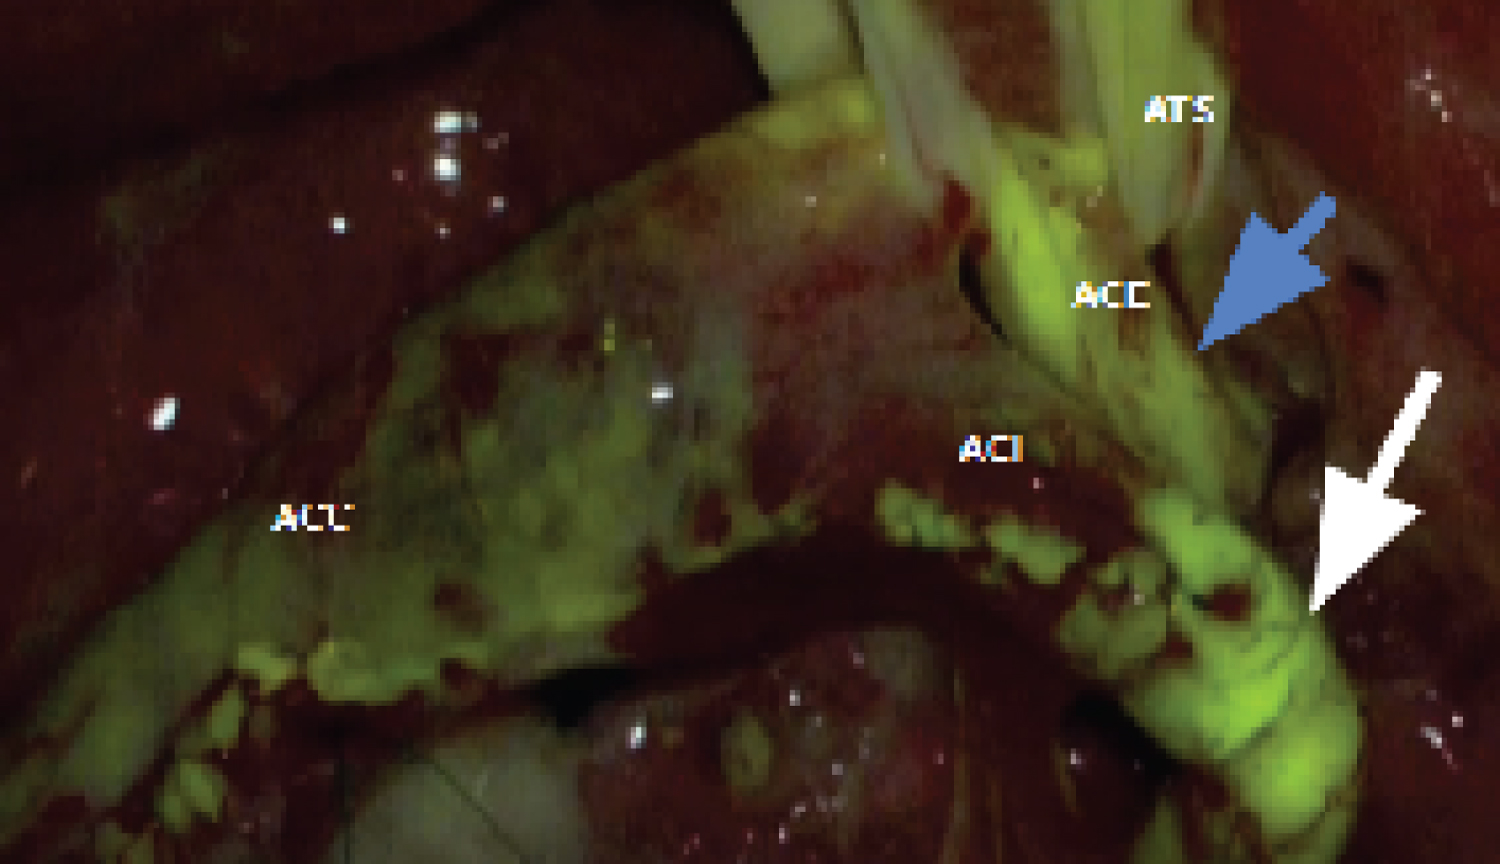

After positioning in the dorsal decubitus with the head slightly extended and turned to the contralateral side, an incision is made at the medial edge of the sternocleidomastoid muscle, extending from the lower neck to the tip of the mastoid process. Once the common carotid sheath is identified and before starting the dissection, the patient is heparinized with 1 milligram of heparin per kilogram of body weight. Heparinization is monitored by the coagulation time, which ideally should be over 200 seconds. Arterial dissection begins at the common carotid artery toward the bifurcation. After exposing the common, internal, and external carotid arteries and the superior thyroid artery (Figure 1), the internal carotid artery (ICA) occlusion tolerance test is performed, where the ICA is clamped for 2 minutes. During this time, the anesthesiologist tests the muscle strength of the contralateral upper and lower limbs, speech, vision, etc. If the patient tolerates ICA occlusion for 2 minutes, the operation proceeds normally. Patients who exhibit intolerance to ICA occlusion for less than 30 seconds are considered to have intolerance to the occlusion test, and the surgery is interrupted.

Figure 1: Exposure of the surgical field.

ACC: Common Carotid Artery; ACI: Internal Carotid Artery; ACE: External Carotid Artery; ATS: Superior Thyroid Artery. View Figure 1

The arteriotomy begins at the common carotid artery and extends towards the internal carotid artery to the distal portion of the atheromatous plaque. The plaque is then progressively excised. Arteriorrhaphy is performed with continuous suturing using polypropylene suture (Prolene 6.0 ® ). Before closing the final stitches, the clamps are progressively removed and repositioned to allow blood flow to eliminate small fragments, clots, or air bubbles. Then, the process of definitive clamp removal begins: The first clamp removed is from the external carotid artery, followed by the common carotid artery clamp, allowing blood to flow towards the external carotid artery for about 2 to 3 minutes. Finally, the clamp on the internal carotid artery is removed. After completing the suturing, fluorescein is injected as a bolus of 5 milligrams per kilogram of body weight without dilution through venous access by the anesthetist, with the aim of documenting distal flow in the internal and external carotid arteries (Figure 2).

Figure 2: Fluorescence under the microscope light after fluorescein. Caption: ACC - common carotid artery; ACI - internal carotid artery; ACE - external carotid artery; ATS - superior thyroid artery. The white and blue arrows demonstrate the presence of distal flow in the internal and external carotid arteries, respectively. View Figure 2